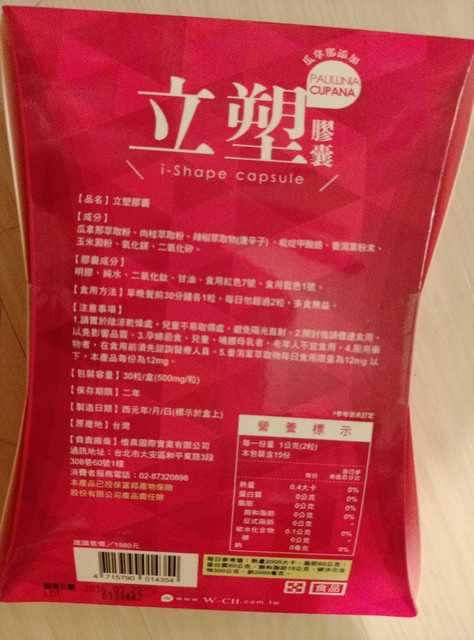

Supercut塑魔纖立塑膠囊的成分有:瓜拿那萃取粉、肉桂萃取粉、辣椒萃取物(唐辛子)、吡啶甲酸鉻、番瀉葉粉末、玉米澱粉、氧化鎂、二氧化矽。

之前上過相關課程,成分表是依照每項成分的多寡來排列順序,排在最前面的就是產品的主要成分!

那我就跟大家分享瓜拿那萃取粉、肉桂萃取粉和辣椒萃取物吧

瓜拿那萃取和辣椒萃取是可以幫助纖體瘦身常見的營養素!

1.「瓜拿那」是原產於亞馬遜流域的一種藤蔓植物,富含酵素可以幫助排便順暢,並且能抑制脂肪分解酵素,此外也有降低食慾的效果喔~~萃取物中含有天然咖啡因,可以提高新陳代謝率以及排出多餘水分!

2.「辣椒萃取物」則是可以幫助體內脂肪燃燒、增加卡路里的消耗,達到防止脂肪積聚的效果

3.「肉桂萃取物」看到肉桂,就想到麥當勞的蘋果派或是手掌麵包,雖然很多人很害怕那味道,但艾哥愛死肉桂了!!!!肉桂在古代被視為是最有價值的東方香料之ㄧ,中世紀時,肉桂的聲望僅次於昂貴的黑胡椒,除了香料和薰香價值, 傳統上肉也被用來治療消化不良、脹氣、關節疼痛、出血和經痛,研究也指出肉桂可以促進新陳代謝喔

食用方式:早晚餐前30分鐘各1粒,每日不超過2粒。(多食無益)

番瀉葉萃取物每日食用限量為12mg以下,